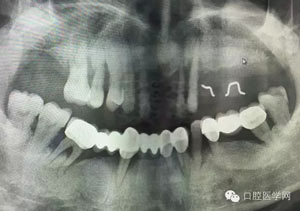

病例1:患者迫切希望保留自己的這一顆牙齒,根尖周陰影比較大,二度松動(dòng).而且旁邊有種植修復(fù)體,和患者溝通好后,治療好后觀察一個(gè)月后冠修復(fù),因?yàn)橛蟹N植的后期修復(fù),所以有了機(jī)會(huì)觀察,術(shù)后三個(gè)月和術(shù)后四個(gè)月,根尖恢復(fù)的還算不錯(cuò),希望能夠繼續(xù)觀察下去.這樣子的病例,做的時(shí)候我們一定要非常的小心,和患者要有充分的溝通以及不同科室的溝通然后決定怎么樣做比較好,假如就是出現(xiàn)了問(wèn)題,到時(shí)候我們也比較好處理些,免得我們自己到時(shí)候不好收?qǐng)觥?/span>